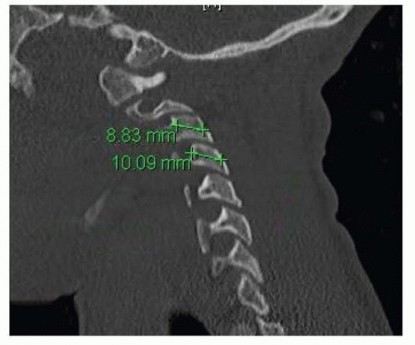

Posterior Cervical Fusion with Lateral Mass Screws DEFINITION The lateral mass is a quadrangular area of bone…